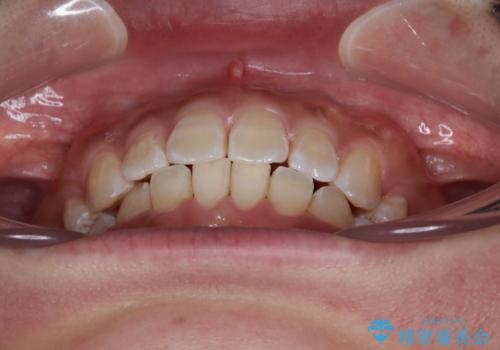

- 前歯の突出感を気にして来院された患者様です。

咬合力が非常に強く、咬合力で前歯が前方に押し広げられており、上下唇に閉じにくさが認められました。

上下左右の第一小臼歯4本を抜歯し、ワイヤー装置にて矯正治療を行うこととしました。

強い咬合力により前歯の隙間がなかなか閉じられず、治療期間は長いものとなりましたが、横顔の印象が大きく変わるほど口元の印象を改善することができました。